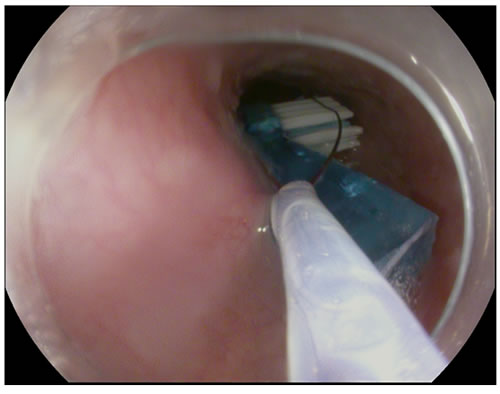

上周末就有一位大叔晨起刷牙太认真,过分用力,一不留神把牙刷刷断了,没等他反应过来又一不小心咽进了肚子里,呕又呕不出来,胸口一阵发闷。大叔赶紧去医院就诊,首诊医院把他转送到市二医院。X光片检查看到一只牙刷头样物体在食管中段,正卡在心脏上方,马上转诊到消化内科。消化内科大夫立即安排胃镜检查,胃镜下见到一只牙刷头正嵌顿在食管狭窄段,用器械完整取出,一量,整整6厘米长。幸好诊治及时,食管粘膜无明显损伤,取出牙刷后大叔胸口不适感完全消散,回家重新刷牙去了。